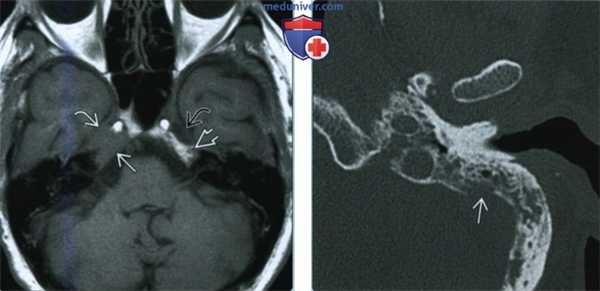

(Слева) При МРТ Т1 с КУ в корональной проекции у пациентки 60 лет, страдающей раком молочной железы и парезом правого лицевого нерва, вдоль чешуи височной кости и каменистого гребня определяется контрастный метастаз в твердой мозговой оболочке с ровными контурами. Опухоль достигает коленчатого ганглия. Обратите внимание на экстракраниальную опухоль с латеральной стороны пораженной чешуи височной кости.

(Справа) При МРТ Т1 с КУ в аксиальной проекции определяется опухоль твердой мозговой оболочки, инфильтрирующая каменистый гребень, распространяющаяся периневрально и достигающая коленчатого ганглия ЧН VII и дна внутреннего слухового прохода.